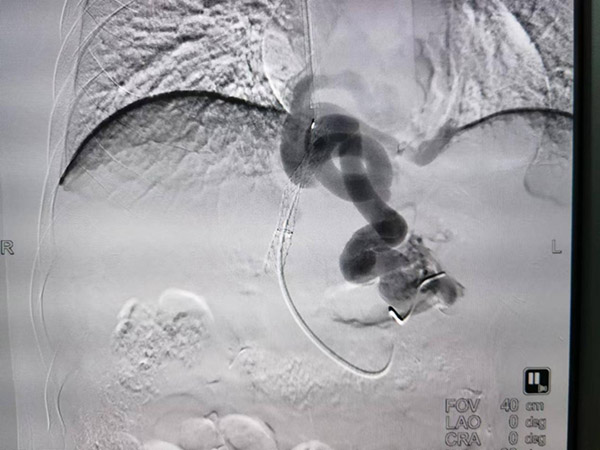

半年前的一个夜晚,急救车的警笛声划破了即将入睡的城市。躺在车上等待治疗的是突发呕血的刘文(化名),急救车飞快地驶向沈阳市第六人民医院,带着他找寻生的希望。 不幸中的万幸,刘文经过出血急诊抢救,情况暂时得到了控制,但这种“控制”并非长久之计。 为确定呕血原因,沈阳六院介入二科对刘文进行了详细检查,发现其患有酒精性肝硬化,而且是个“老病号”了,此次呕血也是肝硬化伴食管胃底静脉曲张破裂导致。 “经过询问,患者有长期大量饮酒的习惯,这是导致其罹患酒精性肝硬化的直接原因。”介入二科主任马轶介绍道,如果不接受进一步治疗,1-2年内患者再出血的概率为60%-70%,病死率可高达33%。 彻 底解决再出血问题成了介入二科医生们的当务之急。经过细致的身体检查及准备工作,马轶对刘文实施了经静脉门体静脉分流术(TIPS)治疗。这是一种微创治 疗手段,患者体表仅有一个针尖大小的创口,且应用局部麻醉,患者全程保持清醒状态,尽可能将手术对身体的损伤降到最低。 这个“小手术”经过医患之间的默契配合,仅用两个小时便顺利完成。术后,刘文身体恢复良好,24小时后便能下床活动,7天后出院回家。经过跟踪回访,现阶段没有出现不适的感觉,也并未发现再出血现象。 无独有偶,最近一位和刘文症状类似,也是呕血后来到沈阳六院就医的患者,引起了医务人员的注意。经过询问,这位长相、年龄都和刘文相近的患者,正是刘文的弟弟刘武(化名)。哥俩平时都好“喝两口”,久而久之便落得个同“病”相怜。 有了之前的成功经验,医患之间对开展治疗都很有信心。经过周密的检查、术前准备,接受了TIPS手术治疗的刘武身体也很快得到恢复,最终顺利出院。 兄弟俩长期饮酒、双双患病呕血是不幸的,但是得到了沈阳六院系统治疗、重获健康的他们又是幸运的。“我们的职责是尽全力为患者提供治疗服务,希望他们都能恢复健康。但我们更愿看到每个人都能在日常生活中珍惜自己的身体,少一些这样的‘难兄难弟’!”马轶由衷地说道。 【专家科普】 1.酒精性肝病是由于长期大量饮酒导致的肝脏疾病。初期通常表现为脂肪肝,进而可发展成酒精性肝炎、肝纤维化和肝硬化。严重酗酒时可诱发广泛肝细胞坏死,甚至引起肝衰竭。 2.门静脉高压症是 指由各种原因导致的门静脉系统压力升高所引起的一组临床综合征,其最常见病因为各种原因所致的肝硬化,常见的临床表现为脾大、脾功能亢进、腹水、门-体侧 枝循环开放,以及并发的食管胃底曲张静脉及其破裂出血、门静脉高压性胃病、肝功能不全、肝性脑病等症状为特征的一组疾病称为门静脉高压症。 3.经颈静脉肝内门腔静脉分流术(TIPS)是 一项治疗门静脉高压症的介入放射学技术。它是指经静脉入路将穿刺系统送至肝静脉,穿刺肝内门静脉一级分支,再将血管支架植入建立肝内门静脉与下腔静脉之间 的分流道,以使整个肝外门静脉系区域的压力显著降低。主要适用于肝硬化门脉高压所导致的食管胃底静脉曲张破裂出血的治疗和预防,以及肝硬化所导致的顽固性 和难治性腹水。 供稿:介入二科 编辑:宣传科 图片:介入二科 【专家简介】 马轶 副主任医师 医学硕士 沈阳六院介入二科主任 兼任国际肝胆胰协会MDT专业委员会委员;中国研究型医院肝癌和门脉高压专业委员会委员;中国中西医结合介入委员会委员;沈阳市肿瘤微创介入委员会副主任委员。参与沈阳市肝癌诊治中心的成立与建设,并担任主要成员。 擅 长领域:多年来致力于肿瘤微创及肝硬化介入诊疗工作,曾多次在北京佑安医院、北京世纪坛医院进修深造。在肝癌、胆管癌、肺癌等肿瘤的介入诊疗方面具有丰富 的临床经验,曾开展沈阳六院首例肝癌介入治疗和首例肺肿瘤以及肾肿瘤的消融治疗。尤其在小肝癌早期诊断,精细化超选择栓塞,复杂疑难病例的影像引导下射频 及微波消融治疗,放射性粒子植入、支架植入治疗以及门脉高压的TIPS治疗方面具有较高造诣。迄今已完成各类肝胆微创手术5000余例。此外对闭塞性动脉 硬化、糖尿病足的腔内治疗也有深刻理解,具有处理复杂疑难病例的丰富经验和技术。